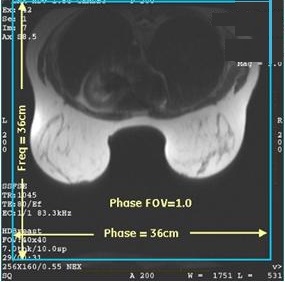

- There are occasions when a “memory not enough, please reduce the scan size” message appears. This most frequently occurs with bilateral multi-phase scans. If this occurs, reduce scan parameter values that affect image size and, therefore, affect the memory required for acquisition (number of phases, slices, matrix size, or Zero-fill Interpolation Processing factor). Alternatively, the Phase FOV > 1 scan parameter can be modified to reduce matrix size without sacrificing resolution but reducing memory consumption. For example, both of the following scan parameters result in a 1 mm2 resolution:

- Freq= 360 and Phase=360 with FOV=36 cm and Phase FOV=1.0

Figure 4. VIBRANT with Phase FOV = 1